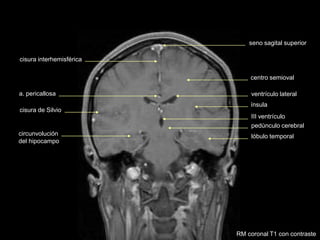

RM coronal T1 con contraste

seno sagital superior

cisura de Silvio

lóbulo temporal

cisura interhemisférica

III ventrículo

ventrículo lateral

centro semioval

ínsula

pedúnculo cerebral

circunvolución

del hipocampo

a. pericallosa